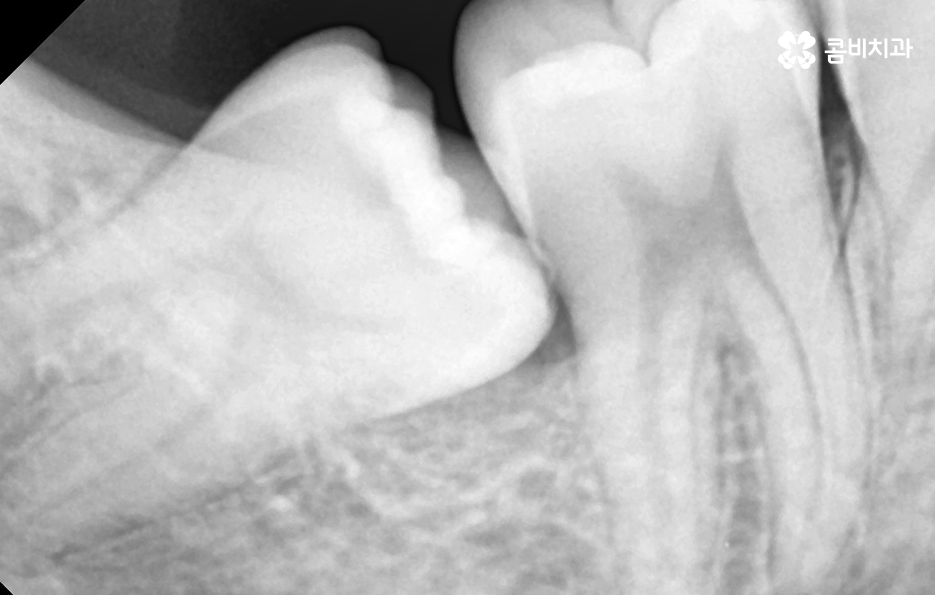

부분매복 사랑니 발치 두 번째 문제는 옆 어금니의 충치와 뼈 손상으로 부분매복 사랑니가 비스듬하게 누운 형태로 자라는 경우가 많은데, 이때 사랑니가 바로 앞 어금니 2번 치아(제2대구치)의 뿌리를 밀어내거나 치아 사이에 음식물이 지속적으로 끼게 될 수 있었어요

이 사이에 끼는 음식물은 아무리 칫솔질을 해도 제거가 어렵기 때문에 앞 어금니가 충치에 취약해지며 실제로 사랑니 때문에 앞 어금니가 충치가 생기고, 결국 큰 신경치료까지 가는 사례가 많은데 더 심하면 앞 어금니 뿌리 주변 뼈가 녹아 앞 치아까지 흔들리는 상태가 되기도 해서 사랑니 자체보다 옆 치아가 더 큰 피해를 보는 경우가 많다는 점이 부분매복 사랑니의 큰 문제점이라 할 수 있어요